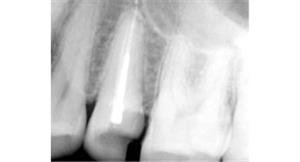

Before

After

A root canal procedure (endodontic treatment) is often required to save an infected tooth. Bacteria can enter a tooth through a cavity or a damaged filling. When this happens, the tooth can become abscessed, meaning the pulp inside the tooth becomes infected. An abscessed tooth can be quite painful and cause swelling in the surrounding gum tissues. If left untreated, it can cause several oral health problems. A root canal procedure removes the infected pulp and any other infected tissues within the tooth.